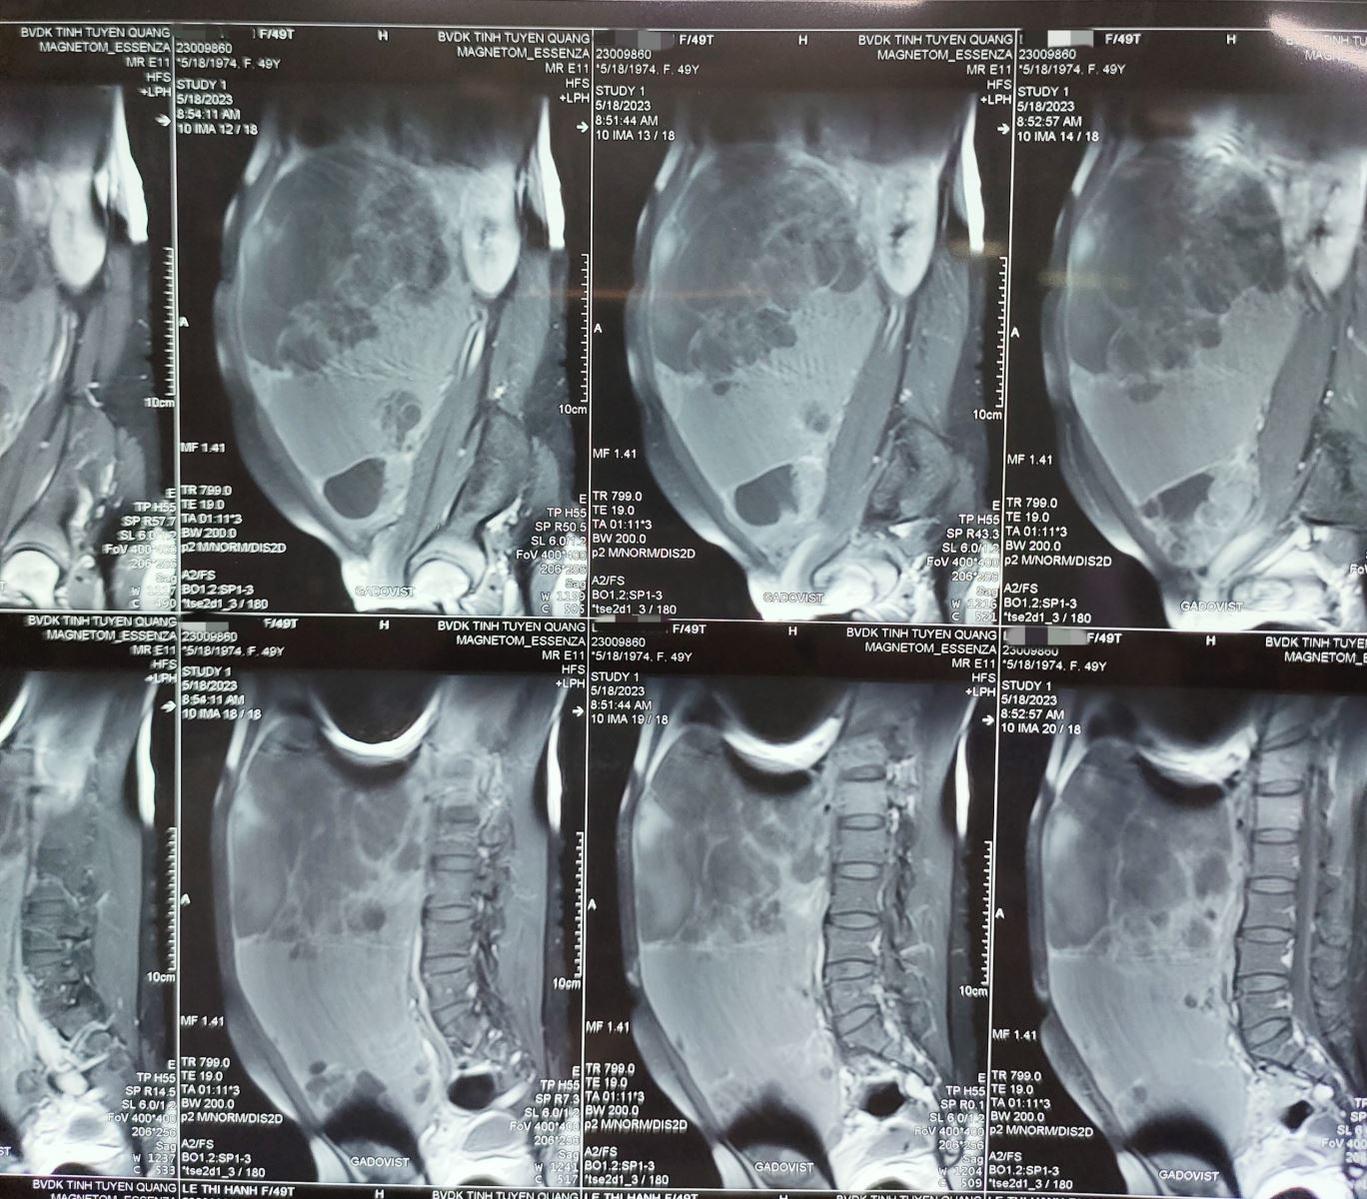

Sau khi được các bác sỹ thăm khám và làm các cận lâm sàng cần thiết, bệnh nhân đã được chẩn đoán có u buồng trứng khổng lồ, kích thước khoảng (25,6x15,7x29,8 cm). Sau khi hội chẩn liên chuyên khoa, bệnh nhân được chuyển về khoa Ung bướu để điều trị và phẫu thuật.

Hình ảnh chụp Cộng hưởng từ (MRI) khối u chiếm gần hết ổ bụng bệnh nhân. Ảnh BVCC